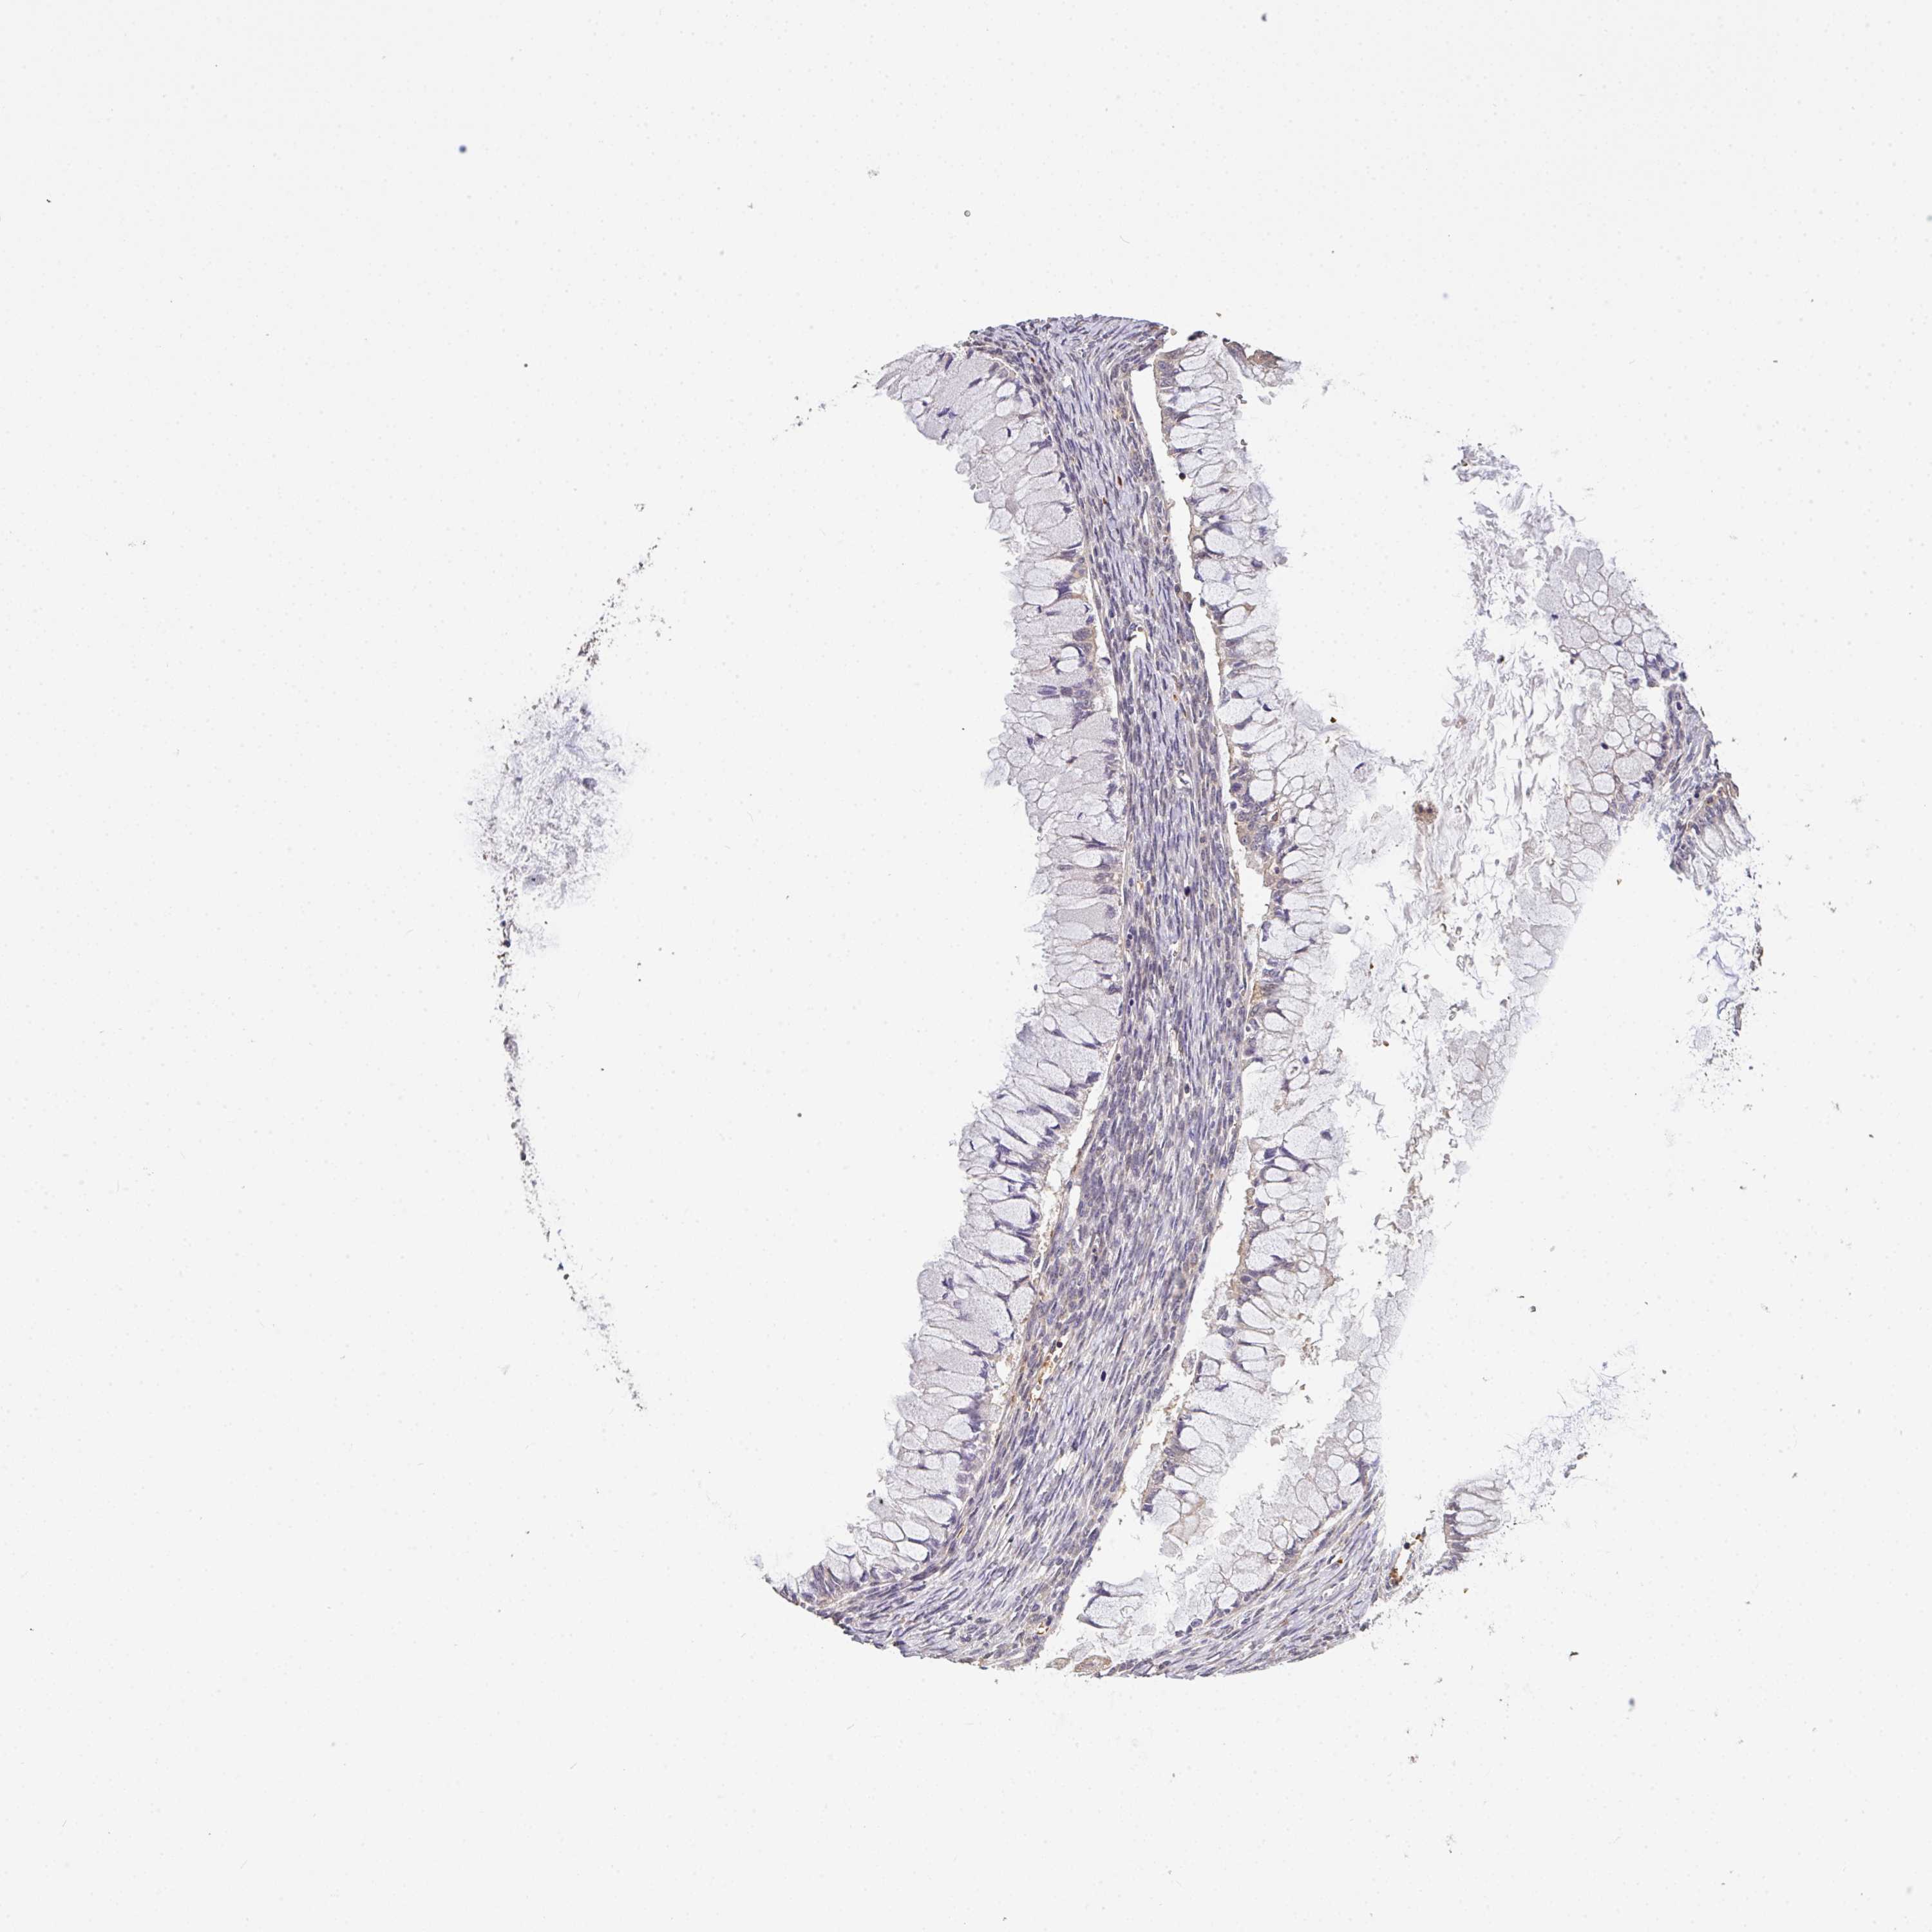

OVARIAN CANCER - Protein expressioni

A mouse-over function shows sample information and annotation data. Click on an image to view it in a full screen mode. Samples can be filtered based on level of antibody staining by selecting one or several of the following categories: high, medium, low and not detected. The assay and annotation is described here.

Note that samples used for immunohistochemistry by the Human Protein Atlas do not correspond to samples in the TCGA dataset.

Antibody stainingi

Antibody staining in the annotated cell types in the current human tissue is reported as not detected, low, medium, or high, based on conventional immunohistochemistry profiling in selected tissues. This score is based on the combination of the staining intensity and fraction of stained cells.

Each image is clickable and will lead to virtual microscopy that enables deeper exploration of all samples and also displays staining intensity scores, fraction scores and subcellular localization as well as patient and tissue information for each sample.

Antibody HPA056632

Staining

High

Medium

Low

Not detected

Intensity

Strong

Moderate

Weak

Negative

Quantity

>75%

75%-25%

<25%

None

Location

Nuclear

Cytoplasmic/membranous

Cytoplasmic/membranous,nuclear

Cystadenocarcinoma, serous, NOS

Cystadenocarcinoma, mucinous, NOS

Carcinoma, endometroid